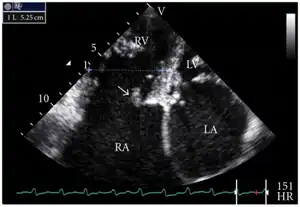

Transthoracic echo: enlargement of the right atrium in TR and mitral valve disease

Transthoracic echo: TR (arrow)